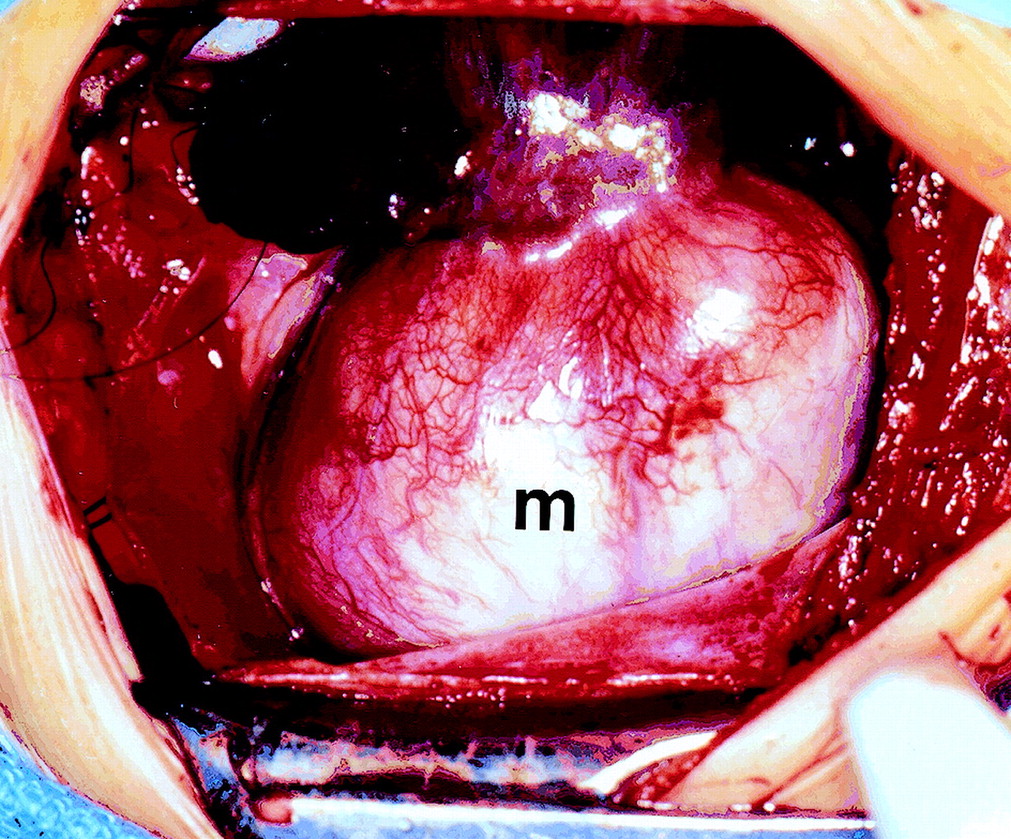

Фиброма может располагаться в разных отделах сердца, наиболее часто - в желудочках или межжелудочковой перегородке. Как правило, она представляет собой солитарное образование диаметром 3-10 см плотной консистенции, имеющее серовато-белую окраску (рис. 65). Опухоль четко отграничена от окружающих тканей, но не имеет капРис. 65. ЭхоКГ фибромы ЛЖ (парастернальная позиция по длинной оси; В-режим) сулы, характеризуется инвазивным ростом. При микроскопическом исследовании центральная часть опухоли состоит из гиалинизирован-ной фиброзной ткани с множественными очагами кальциноза и кис-тозной дегенерации, на периферии находятся веретенообразные клетки типа фибробластов с зернистой цитоплазмой и овальными ядрами с 1-2 ядрышками. Клетки располагаются между пучками коллагеновых волокон, имеющих различное направление.

При росте опухоли часто в патологический процесс вовлекается проводящая система сердца, что обусловливает высокую частоту случаев внезапной смерти.